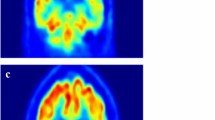

In this paper, we introduce an automatic and robust method to detect and identify Alzheimer’s disease (AD) using the magnetic resonance imaging (MRI) and positron emission tomography (PET) images. AD research as utilized with clinical and computer aid diagnostic tools has been strongly developed in recent decades. Several studies have resulted in many methods of early detection of AD, which benefit patient outcomes and new findings on the development of a deeper understanding of the mechanisms of this disease. Therefore, using the operation of electronic computers to diagnose automatically the incident of AD has served a vital role in supporting clinicians as well as easing significant elaboration on manual and subjectively AD diagnosing of clinicians for the patient’s beneficial outcomes. To this end, we propose a deep learning approach-based model of AD detection applying to MRI and PET images. Individually, we extract non-white matter of brain PET images, which are guided by MRI images as an anatomical mask. Before running the classification module, we build an unsupervised network entitled the high-level layer concatenation autoencoder to pre-train the network with inputs as three-dimensional patches extracted from pre-processed scans. The learned parameters are reused for a well-known convolutional neural network to boost up the training procedure. We conduct experiments on a public data set ADNI and classified a subject into one of three groups: normal control, mild cognitive impairment, and AD. Our proposed method outperforms for AD detection problem than other methods.

Vu, TD., Ho, NH., Yang, HJ. et al. Non-white matter tissue extraction and deep convolutional neural network for Alzheimer’s disease detection. Soft Comput 22, 6825–6833 (2018). https://doi.org/10.1007/s00500-018-3421-5